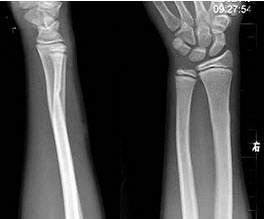

217、单项选择题

男,12岁,右前臂外伤后入院。结合图像,正确的诊断是()

A.Colles骨折

B.孟氏骨折

C.青枝骨折

D.Smith骨折

E.桡骨小头脱位